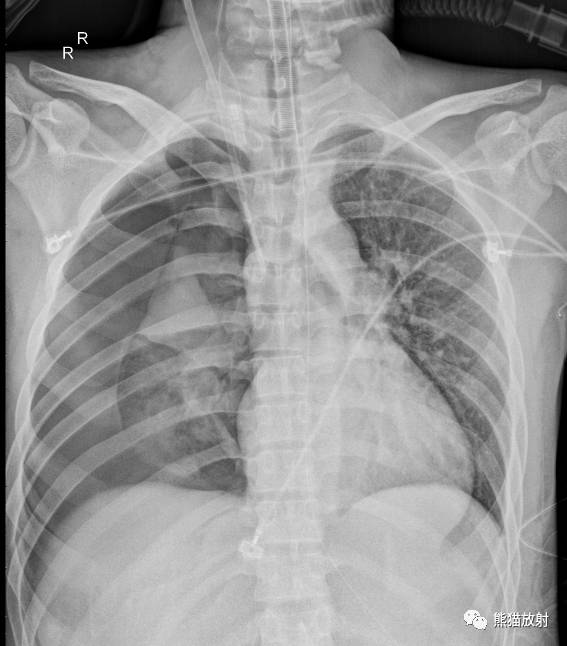

↓ 左肺全肺不张(患者肺野密度增高,胸廓塌陷,气管、纵隔左移) 原因?进一步行CT增强、支气管镜检查。